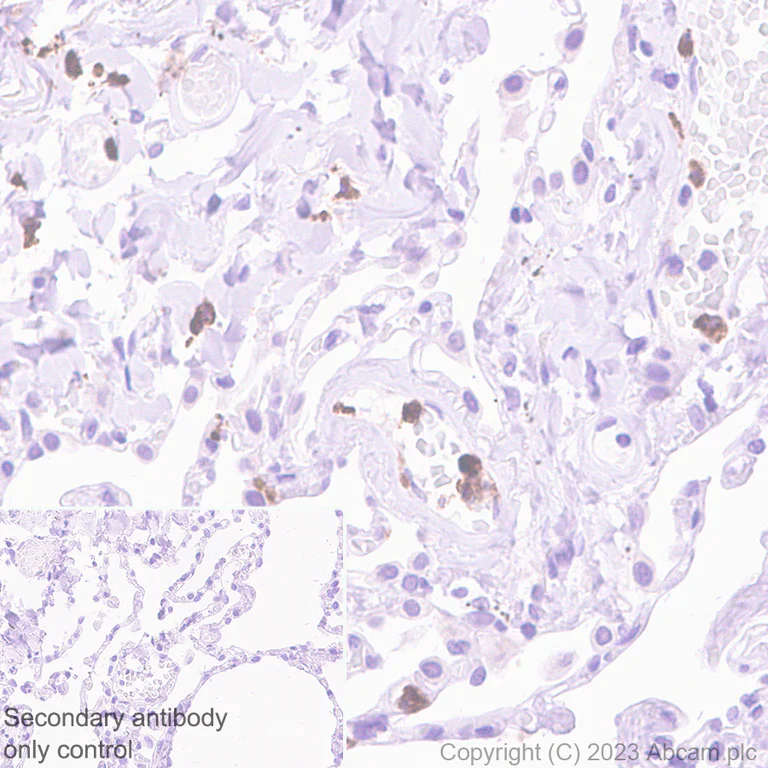

Immunohistochemical analysis of paraffin-embedded Human lung tissue labelling Oncostatin M/OSM with ab307951 at 1/100 (4.85 ug/ml) followed by a ready to use Goat Anti-Rabbit IgG H&L (HRP polymer) (ab214880). Positive staining on scattered immune cells of human lung. The section was incubated with ab307951 at 4°C overnight. Counterstained with Hematoxylin. Secondary antibody only control : Secondary antibody is a ready to use Goat Anti-Rabbit IgG H&L (HRP polymer) (ab214880). Heat mediated antigen retrieval was performed using ab93684 (Tris/EDTA buffer, pH 9.0).